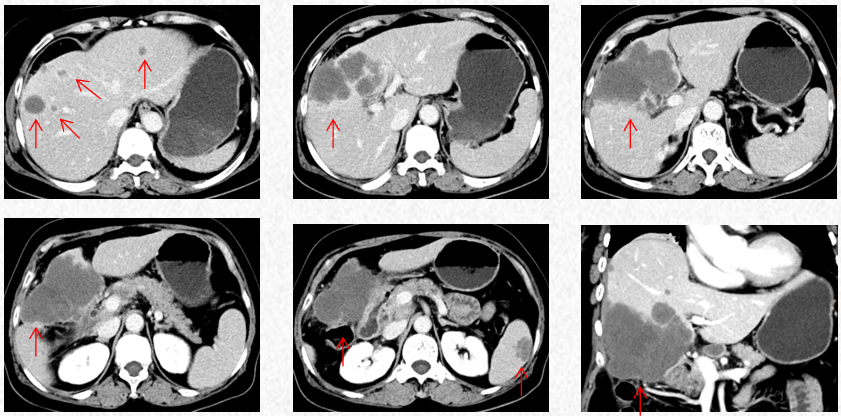

2022-11-30胸腹CT:肝肿物最大横截面积107*80mm(原病灶10*8cm),腹腔淋巴结最大10mm。新发脾脏转移瘤大小27*15mm。

2023-3-19胸腹CT:肝肿物最大横截面积91*60mm,脾脏转移瘤(19*12mm)

2023-5-22胸腹CT:肝肿物最大横截面积86*58mm,脾脏转移瘤(19*12mm)

2023-7-15胸腹CT:肝肿物最大横截面积86*58mm,脾脏转移瘤(19*12mm)